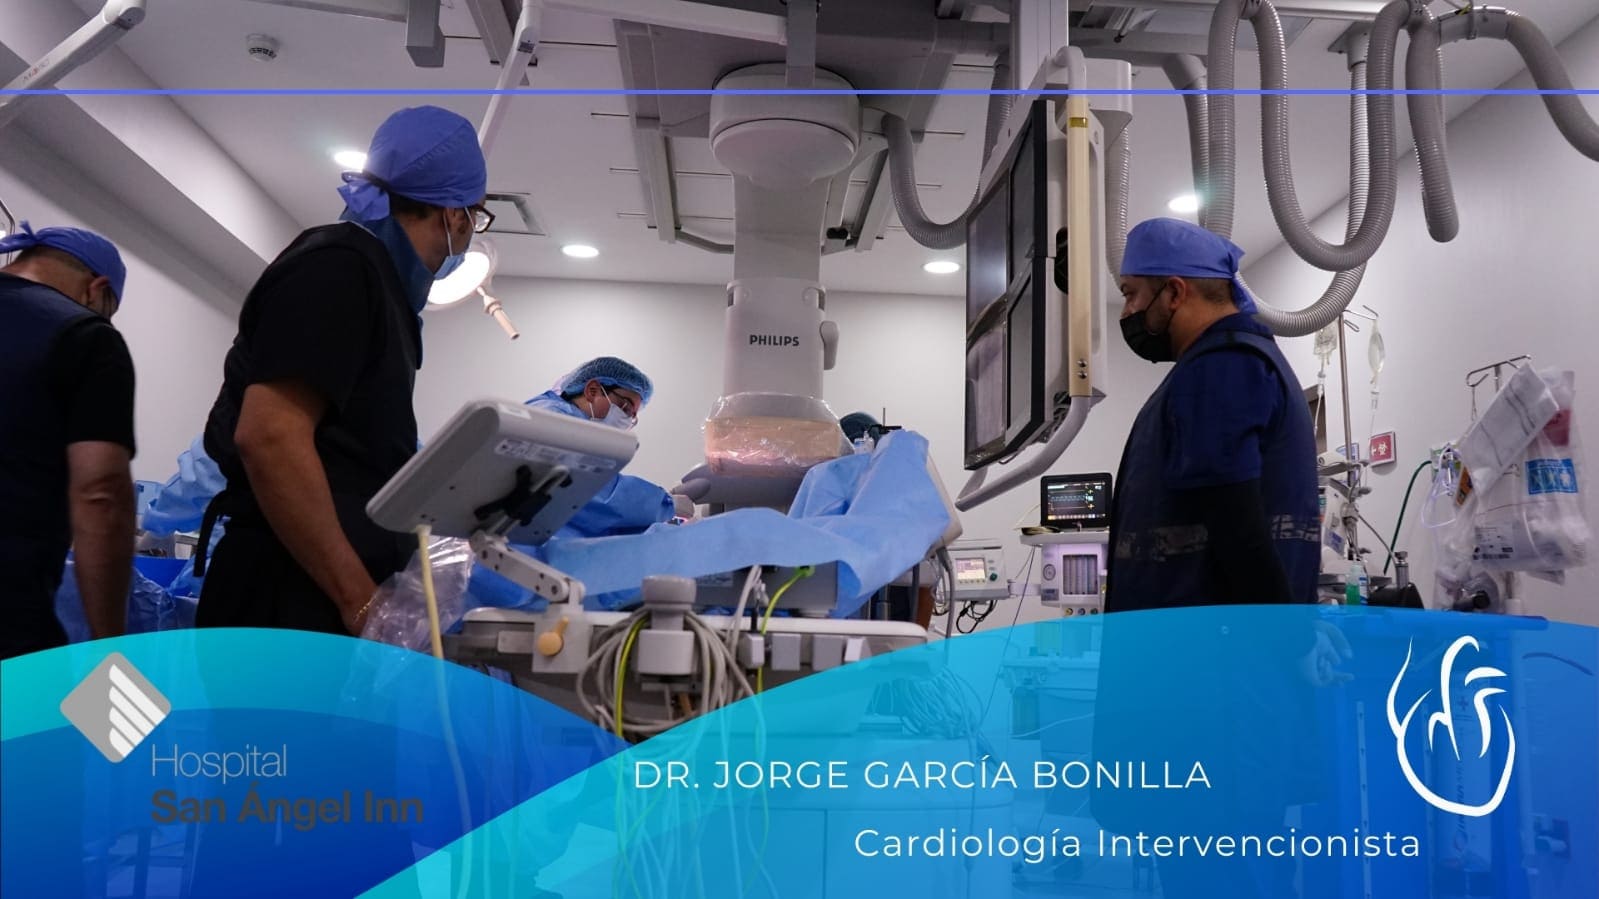

Existen muchas opciones de tratamiento para los problemas cardíacos, desde

medicamentos hasta procedimientos quirúrgicos. Estas opciones pueden ayudar a

controlar los síntomas, prevenir complicaciones y mejorar la calidad de vida.

Conoce mis instalaciones y algunos casos de pacientes en mi